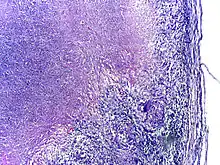

Tuberculosis is classified as one of the granulomatous inflammatory diseases. Macrophages, epithelioid cells, T lymphocytes, B lymphocytes, and fibroblasts aggregate to form granulomas, with lymphocytes surrounding the infected macrophages. When other macrophages attack the infected macrophage, they fuse together to form a giant multinucleated cell in the alveolar lumen. The granuloma may prevent dissemination of the mycobacteria and provide a local environment for interaction of cells of the immune system.[64] However, more recent evidence suggests that the bacteria use the granulomas to avoid destruction by the host's immune system. Macrophages and dendritic cells in the granulomas are unable to present antigen to lymphocytes; thus the immune response is suppressed.[65] Bacteria inside the granuloma can become dormant, resulting in latent infection. Another feature of the granulomas is the development of abnormal cell death (necrosis) in the center of tubercles. To the naked eye, this has the texture of soft, white cheese and is termed caseous necrosis.[64]